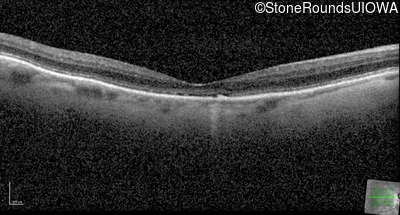

Optical Coherence Tomography - Right - 20/200

Exemplar / OCT Stack